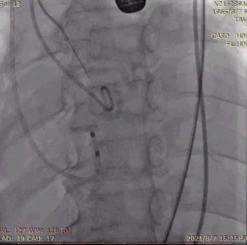

6.经右桡动脉血管鞘送入6F JL4.0指引导管,送 Runthrough至前降支远端,后在GuidezillaII 支撑保护下送 4.0×18mm 支架至 LAD 近段;

7.根据术前评估及球囊预扩情况,选择 26mm 沛嘉 TaurusElite 瓣膜进行植入,第一次展开瓣膜位置偏下,全回收一次再次展开瓣膜,在 130 次/分快速起搏下释放瓣膜,同时将冠脉支架拉至左冠开口外约 9mm 处释放;